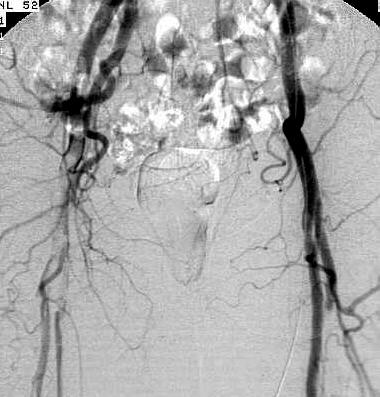

Adult man, 23-years-old,

admitted with pain in the right leg. Physical examination reveals a pale, pulseless,

paralysed leg. This is the third embolism in one year. The patient is in sinus

rhythm

Acute embolism of

the external iliac artery extending in the superficial and profund femoral artery

at the right side as well as a branch of the profund femoral artery at the left

side caused by left atrial myxoma